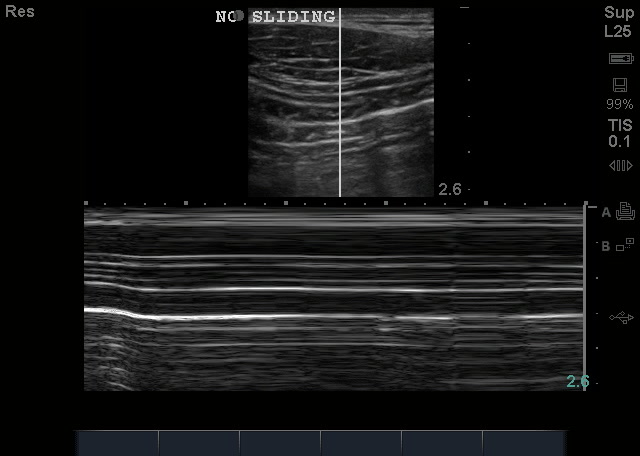

The diagnoses of pneumothorax is essentially the absence of the above findings. You will NOT see air – remember, air is the enemy of US, which means that when there, you will not see what you normally should. You look for the absence of lung sliding, the absence of comet tail artifacts. The absence of the seashore sign on Mmode – called the stratosphere sign.